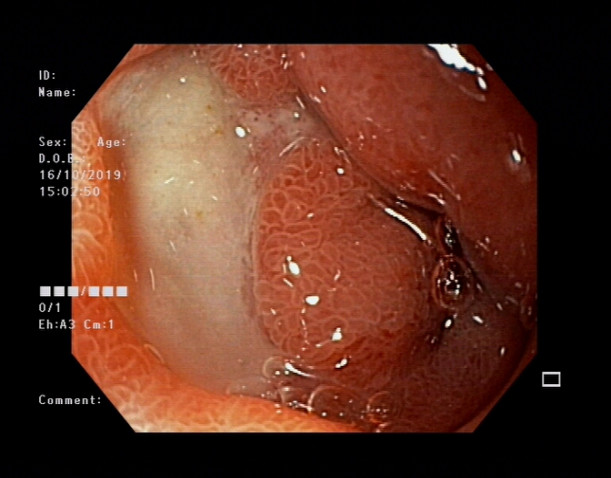

病例:消化性溃疡

患者:余**    性别:男    年龄:68岁     因“腹部疼痛伴恶心、呕吐1天”于2019年10月14日入院,并在我院行胃镜检查显示:胃窦溃疡。

行胃镜检查显示:胃窦溃疡

确诊后,我院消化内科团队开始针对患者情况进行治疗,症状明显得到缓解,无腹痛。

家礼医院消化内科团队提醒:胃溃疡是消化科最常见疾病,发病时患者以上腹部疼痛为主要症状,常呈隐痛、钝痛、胀痛、烧灼样疼痛。胃溃疡多发反复发作、瘢痕形成易形成幽门梗阻,导致食物不能消化,溃疡长期不愈合,特别是年龄45岁以上者有癌变风险。

胃溃疡并发症:消化道出血、癌变、梗阻、胃穿孔。

诊断方式:胃镜是诊断本病有效检查。